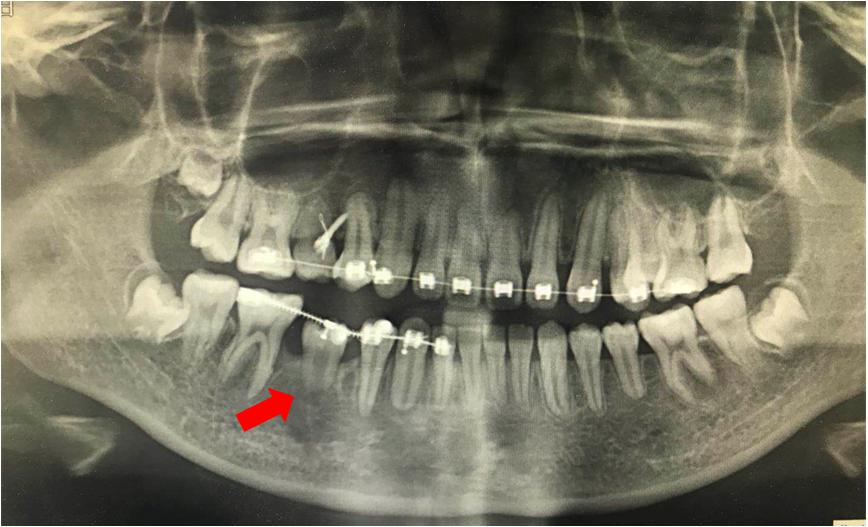

像图片上的牙齿长出来以后埋伏在颌骨内,肉眼看不到牙齿的情况,一般称之为埋伏牙。

1.埋伏牙一直隐藏在颌骨中如果不及时处理,可能对离得近的健康牙齿造成损伤,形成囊肿。

2.埋伏牙还会影响整排牙齿的排列,挤歪其他的牙齿会造成咬合紊乱异常。

一般埋伏牙的处理方式有两种:一是直接拔除,另一种是通过正畸牵引。

直接拔除的情况一般是针对长得歪斜奇怪,有可能会影响正常牙齿健康的才会考虑拔除,如埋伏智齿,影响邻牙健康的话一般都会建议拔除。

正畸牵引的话,这种情况一般是由于埋伏牙是在正常的牙齿数量中。毕竟我们每颗恒牙都十分珍贵,一般牙医是不建议拔除正常的牙齿的。